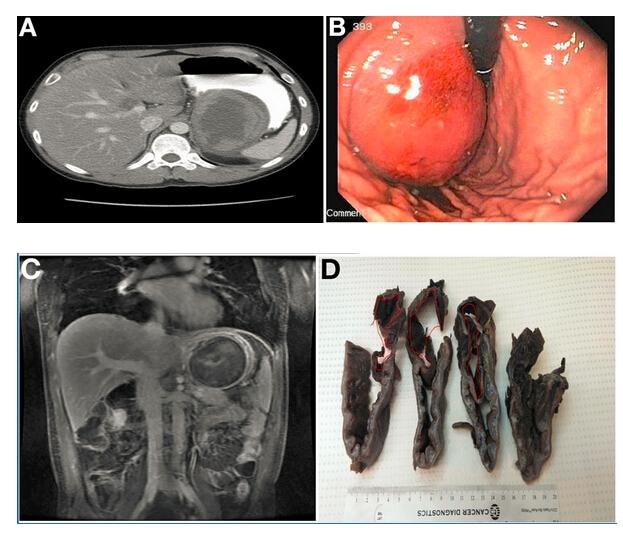

腹部計(jì)算機(jī)斷層掃描(CT)顯示胃底有一9.8×7.4cm不均質(zhì)腫塊(圖A),在隨后的胃鏡檢查中也發(fā)現(xiàn)該腫塊(圖B)。

腹部磁共振成像(MRI)進(jìn)一步明確為界限清楚、不均質(zhì)腫塊,對(duì)比增強(qiáng)(圖C),提高了對(duì)胃腸道間質(zhì)瘤(GIST)的懷疑。計(jì)劃手術(shù)切除。

術(shù)中發(fā)現(xiàn)可疑病變具有定義不明的外科平面和顯著的周圍纖維化,最終行空腸食管Roux-en-y吻合術(shù)。組織學(xué)檢查(圖D)和顯微鏡標(biāo)本(圖E)顯示正確診斷。

令人驚訝的是,胃大部切除標(biāo)本(圖D)檢查發(fā)現(xiàn)在疑似腫瘤的胃壁區(qū)域內(nèi)有扁平囊。這一扁平囊可以拉伸到9×8×4.5cm。胃囊與真實(shí)胃腔之間有一處共同的壁。通過此壁的組織學(xué)切片(圖E)顯示了分隔壁兩側(cè)的平滑肌細(xì)胞層和胃黏膜。這排除了GIST,證實(shí)胃重復(fù)畸形的診斷(GDC)。胃重復(fù)畸形是一種罕見的先天性異常,僅占胃腸道所有重復(fù)囊腫的4%至9%。大多數(shù)病例報(bào)告發(fā)生在兒童中且位于胃大彎處。GDC有以下3個(gè)特點(diǎn):(1)囊腫的壁與胃壁相連,(2)囊腫由平滑肌包圍,通過肌肉與胃壁相連,(3)囊壁排列有胃上皮或其它類型的胃黏膜。